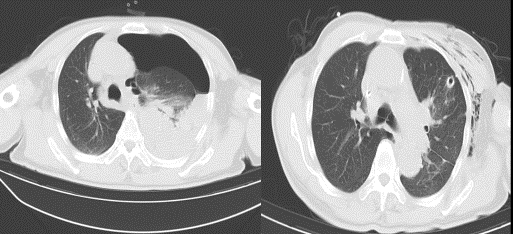

2、CT检查能显示大疱的大小,有助于与气胸的鉴别诊断。03